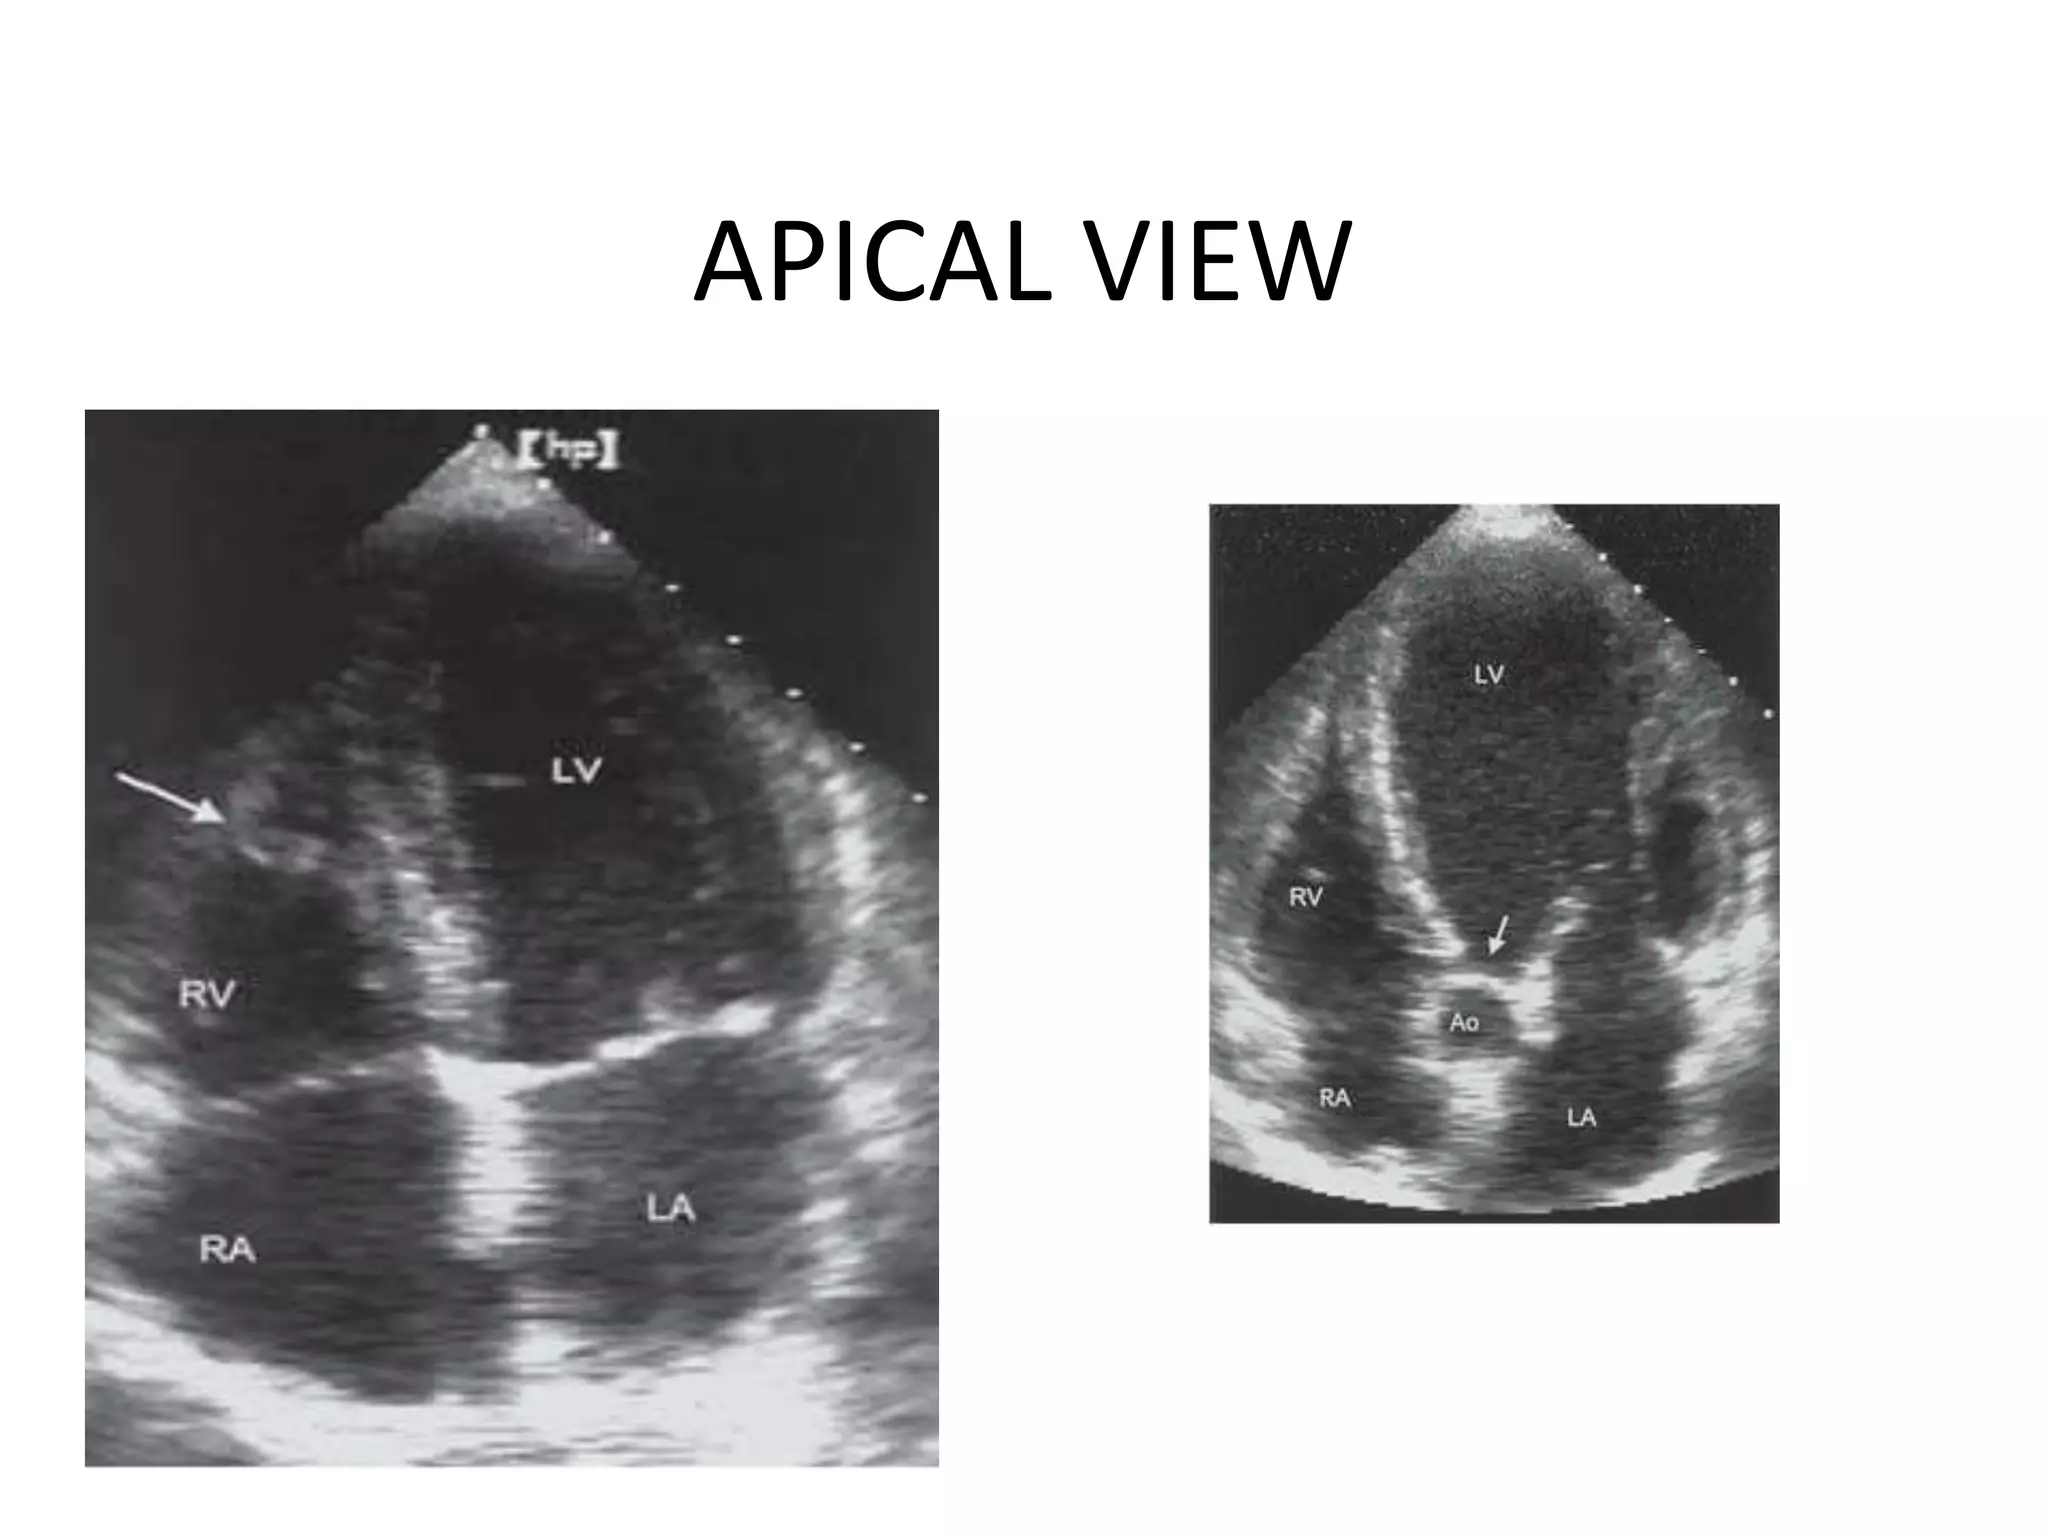

Apical 4-Chamber View (AP4CH)

APICAL VIEW

Apical 2-Chamber View (AP2CH)